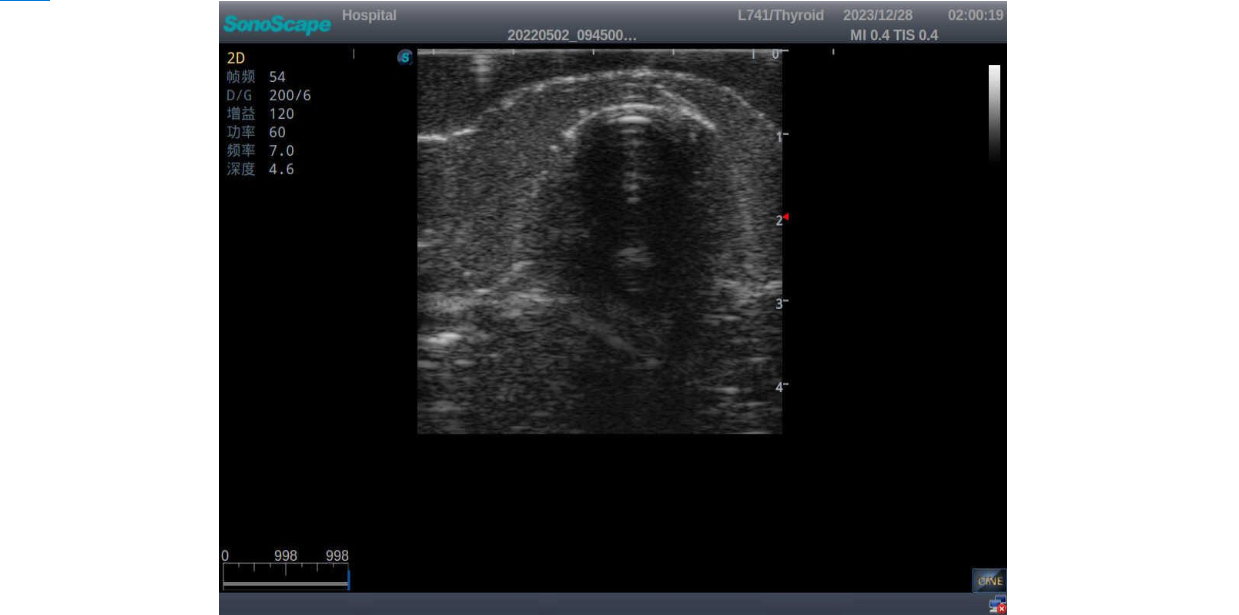

Normal thyroid with homogeneous parenchymal echo and well-defined capsule